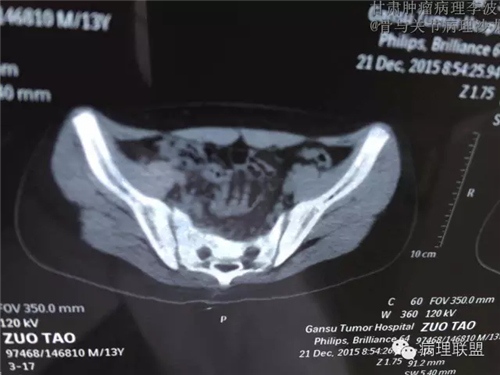

M/14 骶骨骨肉瘤-张惠箴讲解

病例由甘肃肿瘤病理 李波 提供,致谢。